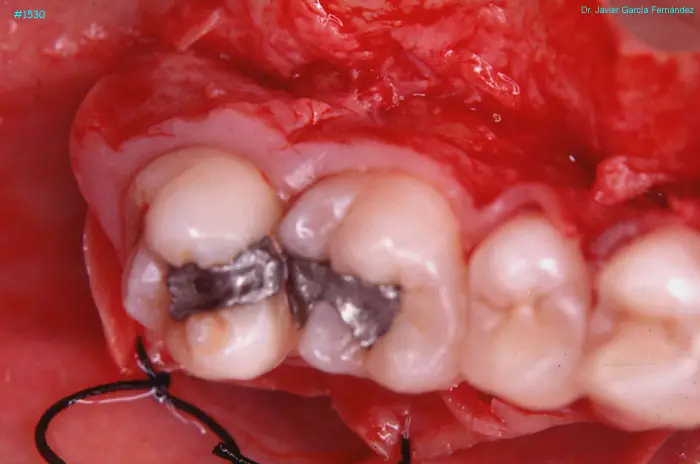

Atlas of Surgical Techniques in Periodontics. Chapter IV. Atlas de Técnicas Quirúrgica en Periodoncia

image 191